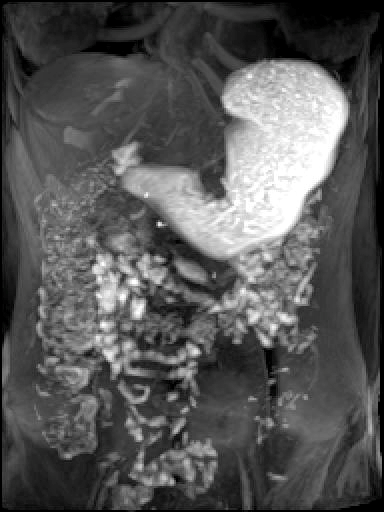

Magnetic Resonance Imaging of the Brain and the Upper Gastrointestinal Tract in Healthy Volunteers and Patients with Gastroparesis

Primary Outcomes Measured: Compare 3D--dimensional gastric peristalsis progression before & after test meals in healthy volunteers and patients with gastroparesis

- Compare colored 3-D heat map of stomach contraction frequency before & after test meals in healthy volunteers and patients with gastroparesis

- Compare pylorus mean opening diameter before & after test meals in healthy volunteers and patients with gastroparesis